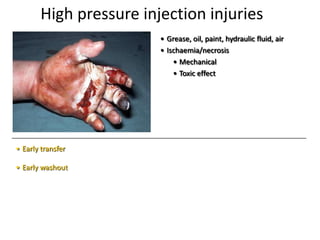

- Conditions that require emergency referral are discussed, such as bleeding, amputation, replantation, compartment syndrome, infections, and high pressure injection injuries. Proper management of these conditions focuses on rapid assessment and treatment to prevent further tissue damage.